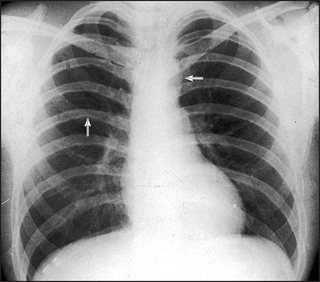

Figure 8.8 Aortic coarctation The classical sign in aortic coarctation is notching of the inferior aspects of the ribs (arrow on left). This is due to hypertrophy of the intercostal arteries in which retrograde flow from the axillary collaterals is taking blood back to the descending aorta. Because of the increased resistance to the left heart flow, left ventricular hypertrophy and then failure can occur. Failure causing cardiac enlargement has not yet occurred in this patient. The arrow on the right indicates a smaller than normal aortic knuckle.